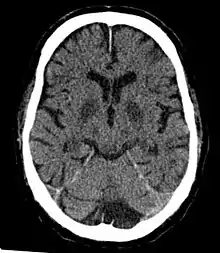

CT in a person after generalized hypoxia.

However, if blood flow cannot be increased or if doubled blood flow does not correct the problem, symptoms of cerebral hypoxia will begin to appear. Mild symptoms include difficulties with complex learning tasks and reductions in short-term memory. If oxygen deprivation continues, cognitive disturbances, and decreased motor control will result.[6] The skin may also appear bluish (cyanosis) and heart rate increases. Continued oxygen deprivation results in fainting, long-term loss of consciousness, coma, seizures, cessation of brain stem reflexes, and brain death.[7]